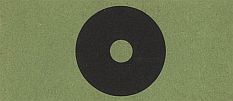

Можно убедиться в наличии слепого пятна, рассматривая любой из рис. 11, 12 и 13. На этих рисунках слепое пятно для правого глаза обнаруживается правее центрального луча, а для левого — левее. При этих условиях в первом случае пропадает правая часть рисунка, а во втором левая. Поэтому для правого глаза надо установить рисунок так, чтобы прямо против глаза находилась левая часть рисунка (например, центральный кружок рис. 11 и 12 или крест рис. 13), а для левого — правая часть рисунка. Затем, если необходимо, удалять или приближать рисунок, или сдвигать его понемногу в сторону, пока не будет достигнут четкий эффект.

Рис. 11

Рис. 12

Рис. 13. Закрыть левый глаз и посмотреть правым на фигуру, изображенную слева, держа рисунок на расстоянии 15–20 см от глаза. При некотором положении рисунка относительно глаза изображение правой фигуры перестанет быть видимым.

Рис. 11 и 13 позволяют обнаружить слепое пятно и правого, и левого глаза.